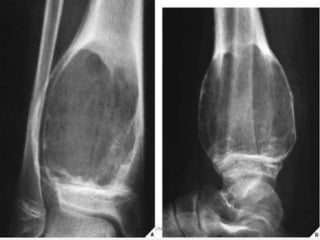

Osteochondroma. On this lateral view of the ankle, a

benign osteochondroma is seen projecting posteriorly

on a stalk. The end (arrows) is often covered with a

cartilaginous cap. These lesions always occur near a

UM

jo

Yint but point away from it.

MRI

MRI is best at assessing

cartilage thickness (and thus

assessing for malignant

transformation), presence of

oedema in bone or adjacent

soft tissues and visualising

neurovascular structures in the

vicinity.

The cartilage cap of

osteochondromas appears the

same as cartilage elsewhere,

with intermediate to low signal

on T1 and high signal on T2 and

STIR weighted images.

A cartilage cap of over 1.5cm in

thickness is suspicious for

malignant degeneration.